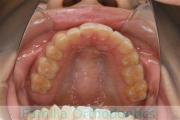

No.23V-061

- 主な症状:

- 叢生

- その他の症状:

- 上下顎前突

- 年齢:

- 23歳

- 性別:

- 女性

- 抜歯部位

- 上:

- 44

- 下:

- 主な使用装置:

- FEA 022

- 治療にかかった費用:

- 88万円

でこぼこを綺麗に並べたいということで来院されました。上下左右から小臼歯を抜歯して、マルチブラケット法を2年半、30回程度通院していただいて行いました。

かなり強い叢生(でこぼこ、凹凸、ガタガタ)のため、保定をしっかりしないと後戻りのリスクが高いケースといえます。

- ≫治療後

-

上顎

下顎

前歯の関係など

右側

正面

左側